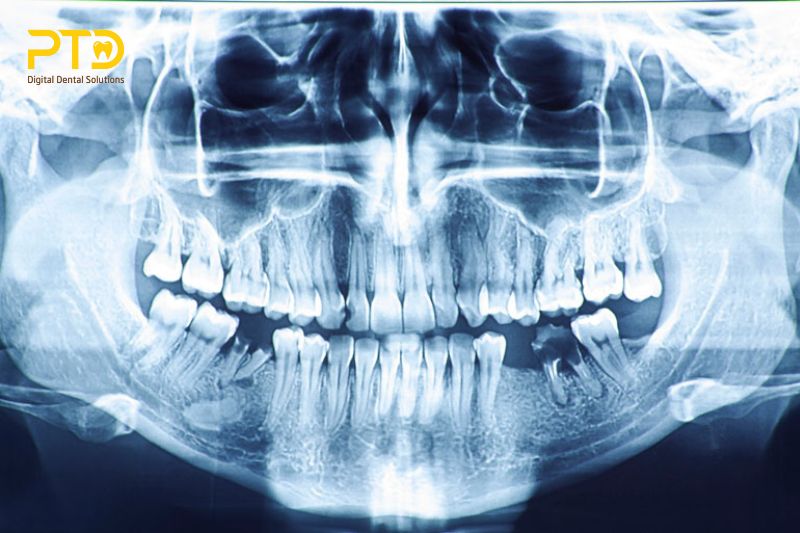

Chụp X-quang nha khoa là quá trình sử dụng máy chụp X quang để tạo ra hình ảnh của răng, xương, và mô mềm xung quanh. Điều này giúp bác sĩ phát hiện những vấn đề như sâu răng, viêm nướu, hay những cấu trúc ẩn như răng khôn. Hình ảnh thu được sẽ là cơ sở để đưa ra quyết định chẩn đoán và lên kế hoạch điều trị phù hợp.

Máy chụp X-quang nha khoa sử dụng tia X, có khả năng xuyên qua dịch lỏng và mô mềm để tạo ra hình ảnh chi tiết về cấu trúc nội bộ của miệng. Do đó giúp bác sĩ quan sát những chi tiết khó nhận biết bằng mắt thường, n hư khoang hở hay tình trạng mất xương. Máy chụp X-quang nha khoa là thiết bị nha khoa quan trọng giúp bác sĩ đưa ra chẩn đoán chính xác và nhanh chóng.

Máy chụp X-quang hỗ trợ nha sĩ phát hiện các vấn đề về răng miệng mà không thể nhìn thấy bằng mắt thường. Nhờ tia X, hình ảnh chi tiết về cấu trúc nội bộ của miệng, kể cả những vùng khó tiếp cận như khoang hở hay tình trạng mất xương, trở nên rõ ràng.

Phát hiện bệnh lý nha chu

Máy chụp X-quang giúp nha sĩ phát hiện bệnh lý nha chu, bao gồm các vấn đề về mô liên kết, nướu và xương. Việc nhìn thấy tình trạng mất xương xung quanh răng và các túi viêm giúp đánh giá và xác định mức độ tổn thương, từ đó đưa ra quyết định về phương pháp điều trị.

Đánh giá khối u và bệnh lý liên quan xương hàm

Máy chụp X-quang hỗ trợ trong việc đánh giá và xác định khối u, bệnh lý hay tổn thương vùng hàm. Điều này giúp nha sĩ tư vấn và lên kế hoạch điều trị kịp thời, đồng thời ngăn chặn sự lây lan và cải thiện dự đoán lâm sàng.